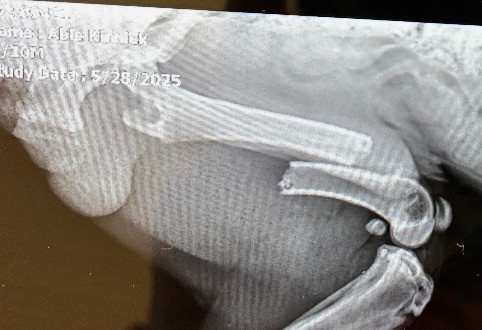

I don’t ask for help much that’s not the person I am . But my yellow lab puppy broke his femur bad doing what he loved playing out side with stick and ball . The last resort is amputation but I would be devastated to see that happen since his little brother loves playing with him